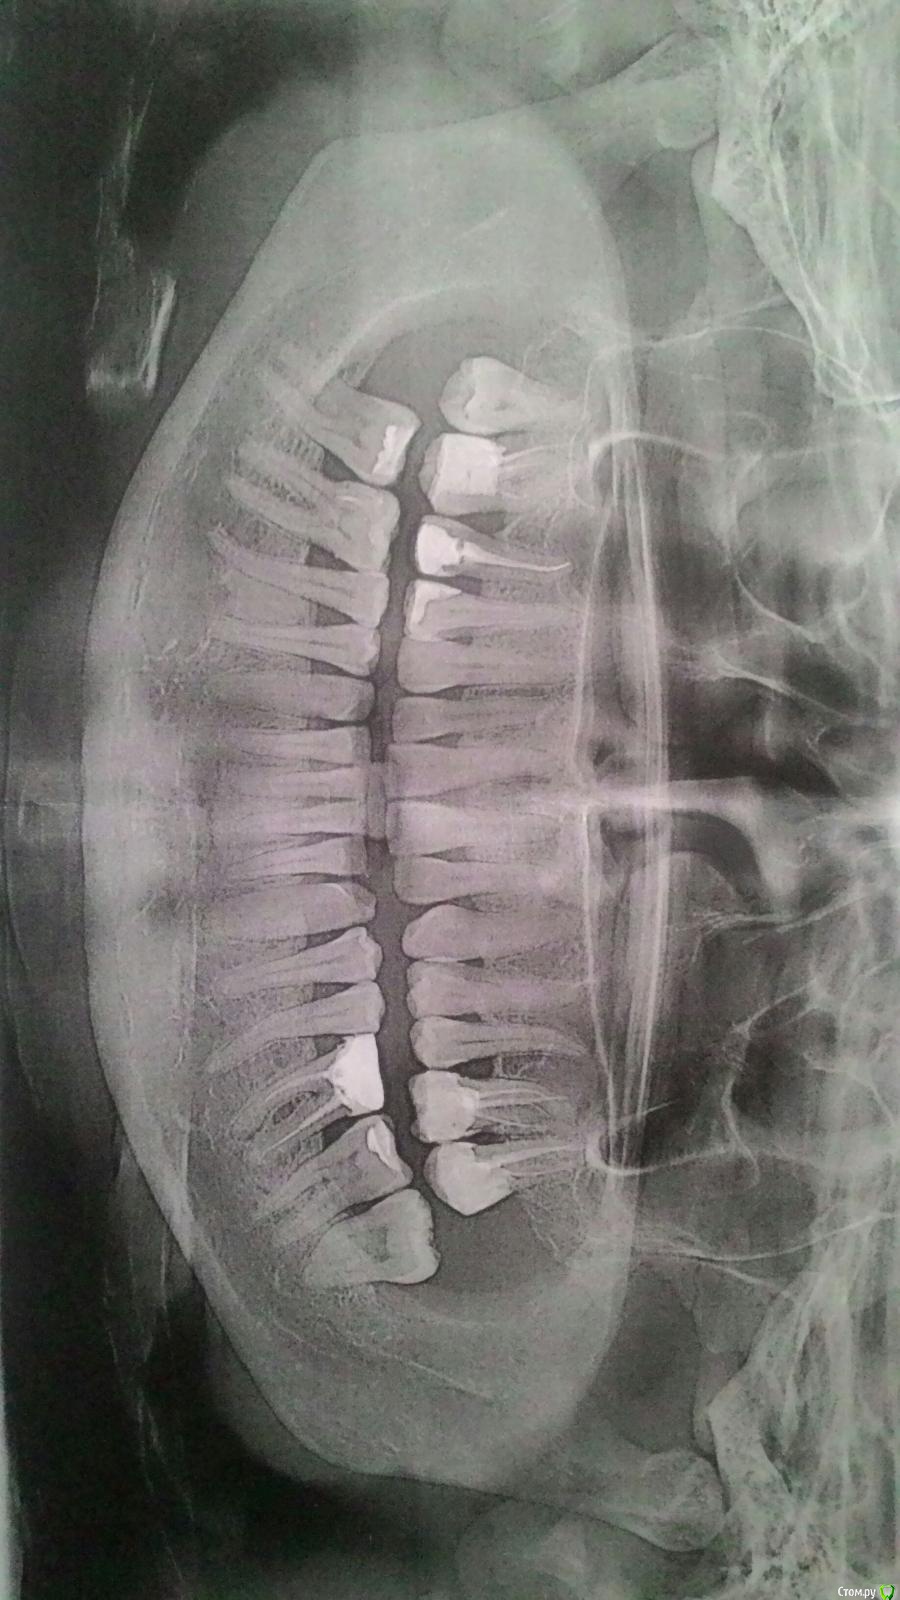

Dkat Опубликовано 10 мая, 2018 Поделиться Опубликовано 10 мая, 2018 (изменено) Добрый день, подскажите, возможно ли лечение нижней левой 6ки или только удаление?Верхние 6,7 - перелечивать? Изменено 10 мая, 2018 пользователем Dkat Ссылка на комментарий

red_butler Опубликовано 11 мая, 2018 Поделиться Опубликовано 11 мая, 2018 Добрый день, подскажите, возможно ли лечение нижней левой 6ки или только удаление? кисты нет 1 Ссылка на комментарий

Dkat Опубликовано 11 мая, 2018 Автор Поделиться Опубликовано 11 мая, 2018 Неожиданно...В 2х клиниках диагностировали кисту...А что там тогда - разряжение костной ткани? И что порекомендуете делать с зубом? Ссылка на комментарий

red_butler Опубликовано 11 мая, 2018 Поделиться Опубликовано 11 мая, 2018 И что порекомендуете делать с зубом? лечить и протезировать 2 Ссылка на комментарий

red_butler Опубликовано 11 мая, 2018 Поделиться Опубликовано 11 мая, 2018 они не берутся лечить((( Мы видим только снимок, к тому же перевернутый, очно может выглядит хуже1.6 2.6 2.6 нужно смотреть очно, возможно придется снимать пломбы 1 Ссылка на комментарий